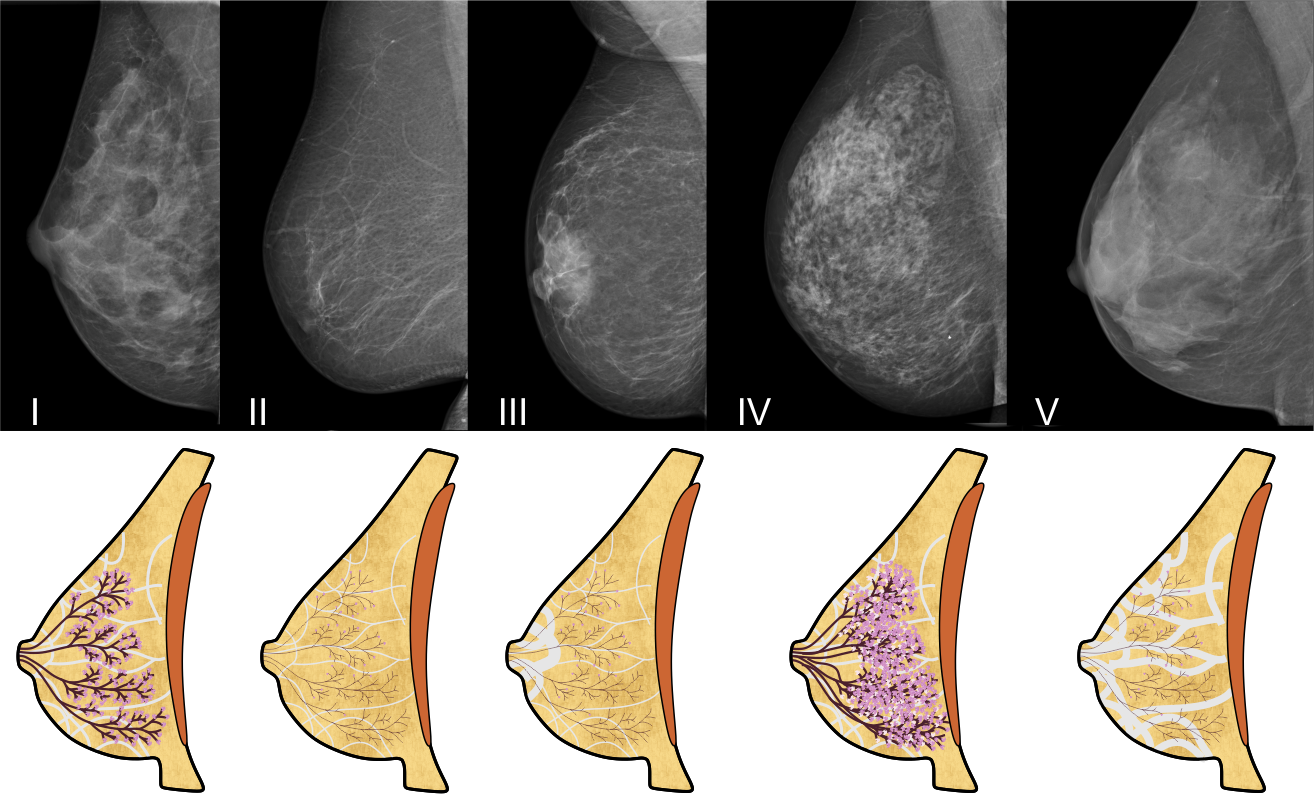

Die fünf Typen ('parenchymal patterns') der Brust in der Mammographie

Das folgende Bild zeigt typische Beispiele für die fünf Brusttypen in der Mammographie:

und ihre Zusammensetzung durch die vier Gewebearten Fettgewebe, Bindegewebe, Milchgänge und Drüsenläppchen

Der Brusttyp I zeigt eine ausgewogene Verteilung der vier Gewebearten, wie sie bei den meisten jungen Frauen anzutreffen ist. Dieser Typ geht mit zunehmendem Alter, besonders nach dem Wechsel, über in den Brusttyp II. Dabei bildet sich die Brustdrüse zurück und das Bindegewebe wird dünner, das Fettgewebe hingegen vermehrt sich. Manchmal bleibt ein größerer Bindegewebsrest hinter der Brustwarze zurück, dann spricht man vom Typ III.

Brusttyp IV und V sind durch das deutliche Überwiegen einer Gewebeart gekennzeichnet. Bei Brusttyp IV überwiegt das Brustdrüsengewebe, und hier vor allem die Milchdrüsenläppchen. Sie sind meist größer und auch in ihrer Anzahl vermehrt. Bei Brusttyp V überwiegt das Bindegewebe. Beiden Brusttypen ist gemein, dass sie sich im Gegensatz zu Typ I im Laufe des Lebens kaum verändern. Das zeigt auch das obige Bild: Die Mammographie des Typs I stammt von einer 35 jährigen Frau, die übrigen Aufnahmen von Frauen zwischen 68 und 72 Jahren.